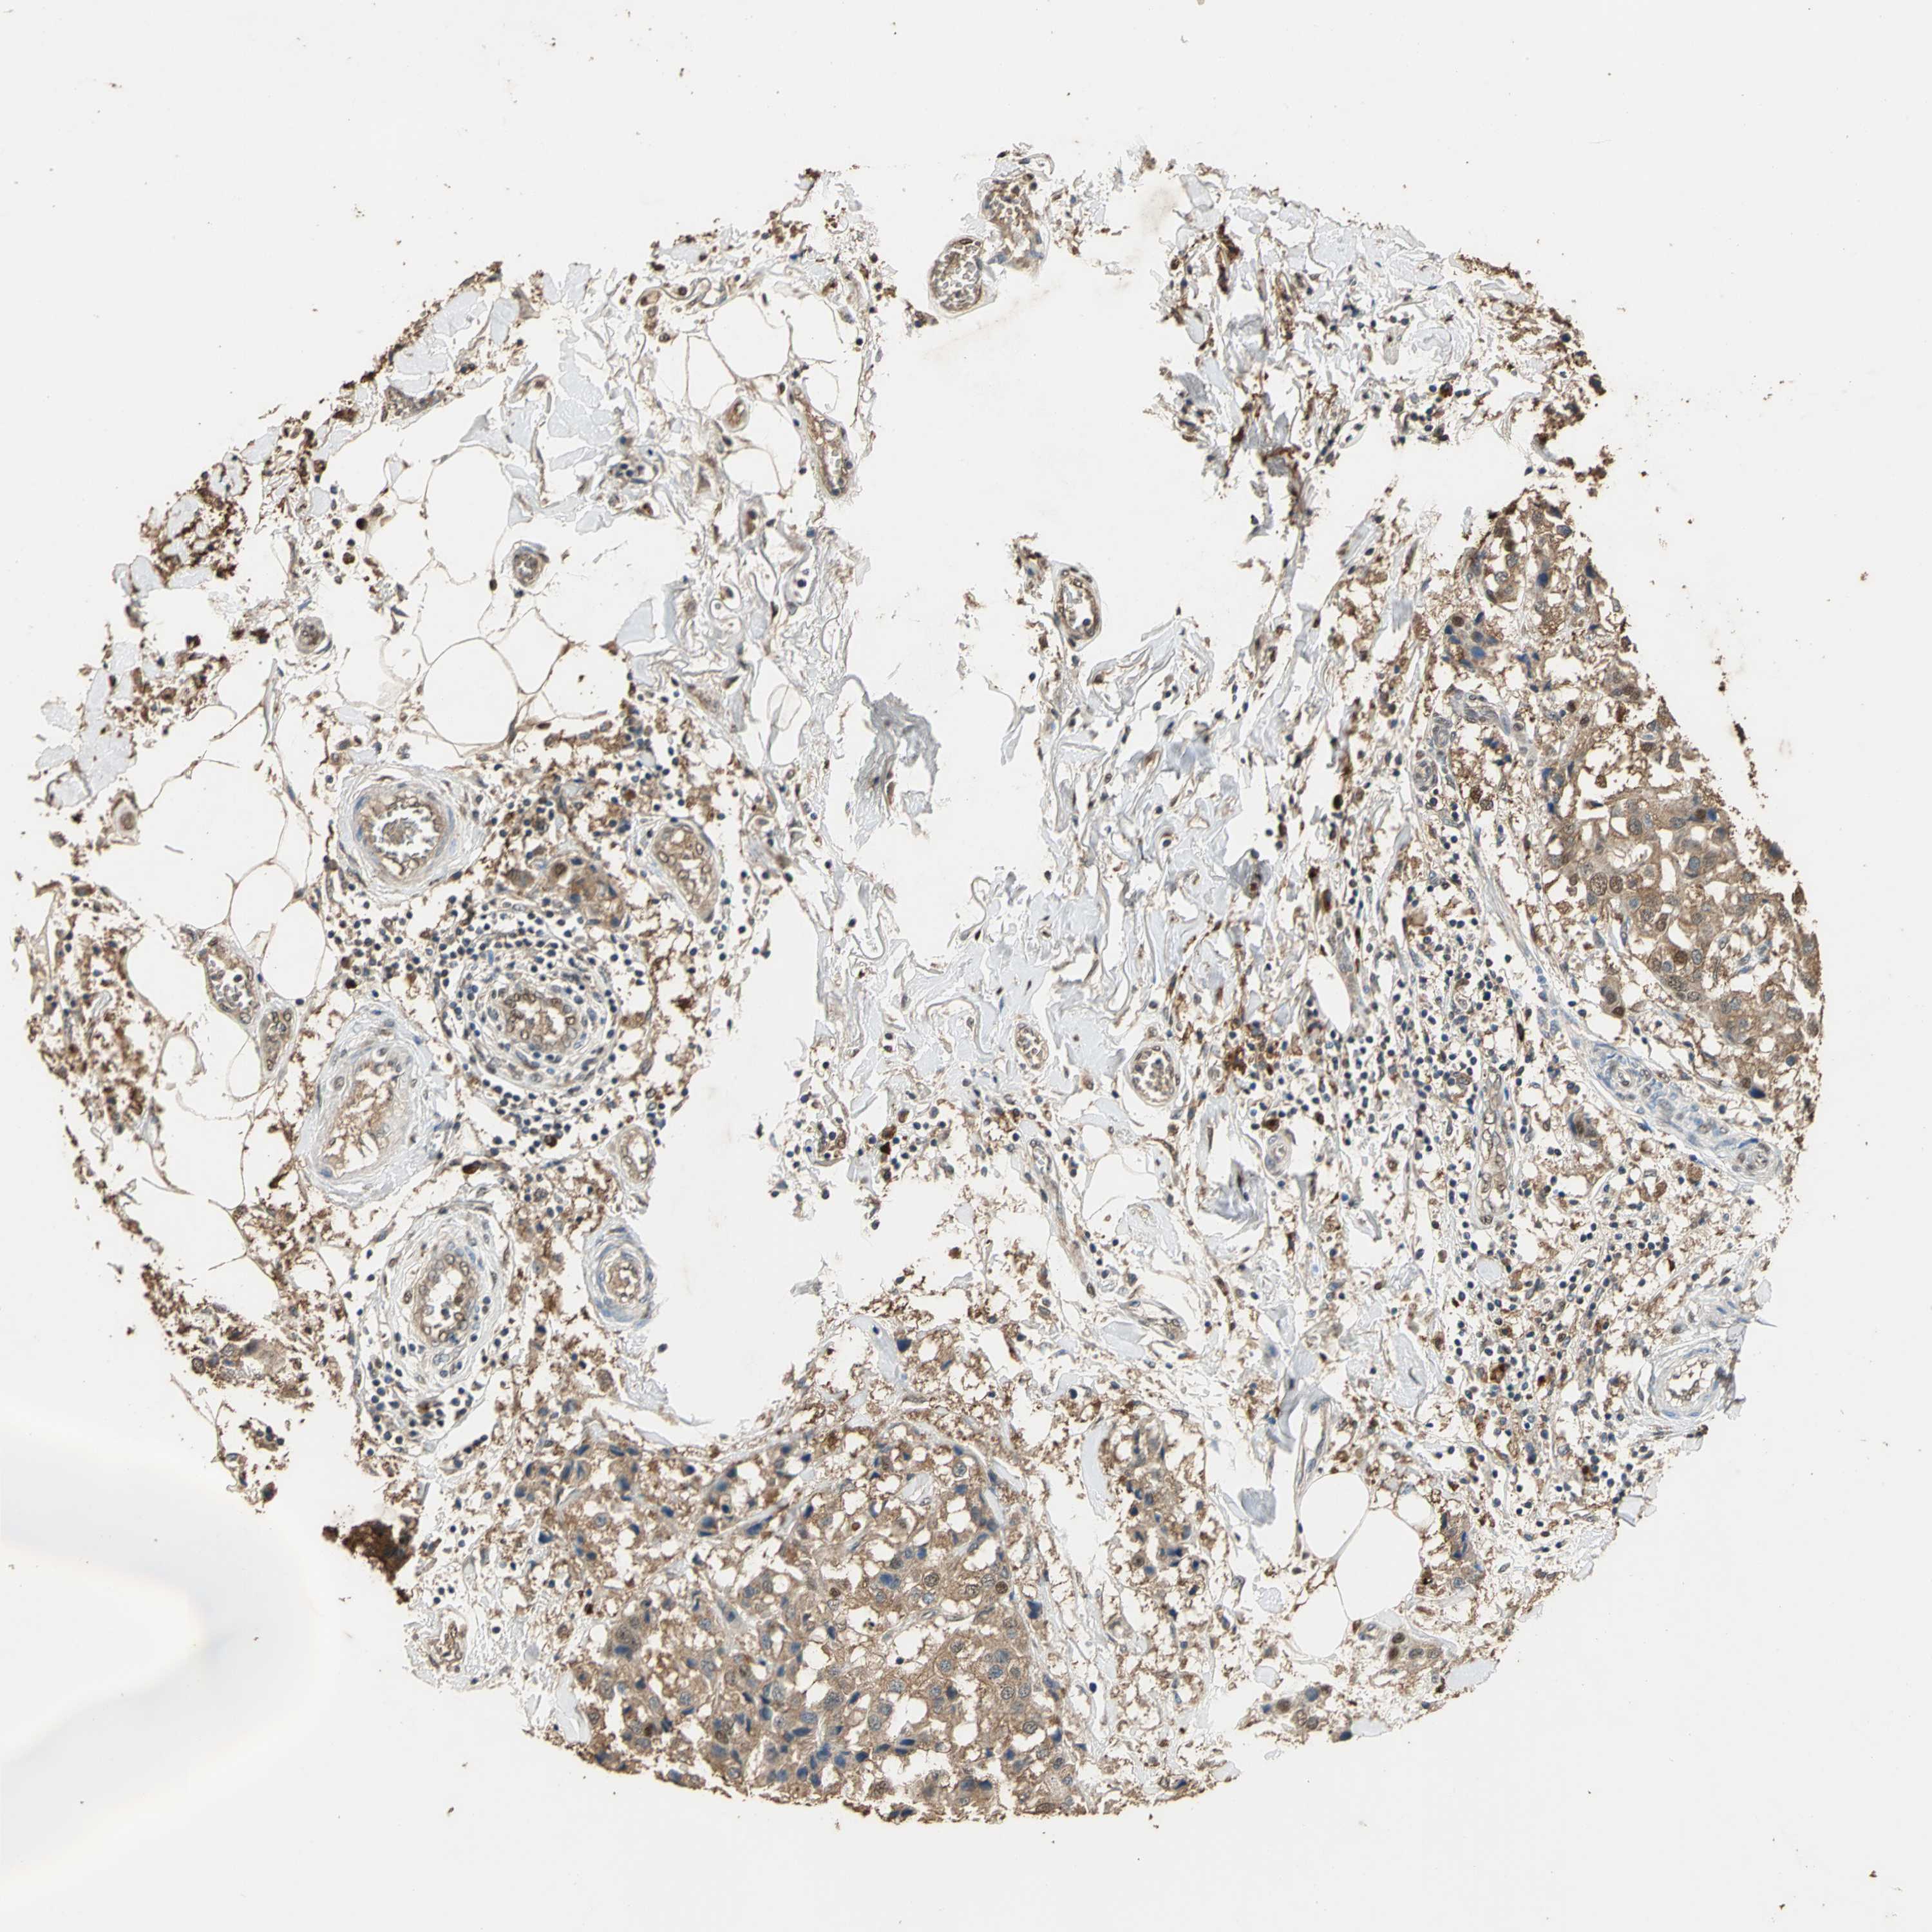

BRCA TCGA BRCA VALIDATION PROTEIN EXPRESSION

ANTIBODIES

AND

VALIDATION